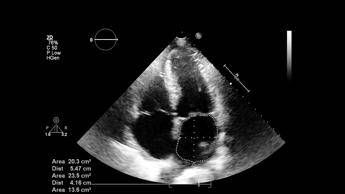

La pubblicazione del documento - riporta una nota - sancisce un dato di fatto: l'ecografia polmonare si sta rivelando uno strumento prezioso nella pratica clinica quotidiana. "Si tratta di un documento che sottolinea l'importanza dell'ultrasonografia polmonare per migliorare la gestione clinica in ambiente ospedaliero - spiega il presidente Sirm, Andrea Giovagnoni - La Lus può ottimizzare i percorsi diagnostici, riducendo l'uso di tecniche invasive o radiologiche più costose e rischiose". Il testo "rappresenta uno strumento prezioso per decisioni cliniche rapide nelle emergenze, con l'obiettivo prioritario di salvaguardare sempre la sicurezza del paziente".

"L'ecografia polmonare è una tecnica che permette di valutare le più comuni patologie polmonari tipiche dei neonati nati anche prima del termine - illustra il presidente Sin, Massimo Agosti - Consente al neonatologo di integrare il quadro clinico dei neonati critici con una metodica diagnostica efficace, rapida e facilmente riproducibile, atta ad assistere i medici nella gestione di patologie spesso rapidamente progressive e tempo dipendenti. Possiede un'alta accuratezza diagnostica, non utilizza radiazioni ionizzanti ed è facilmente adattabile al contesto della Terapia intensiva neonatale poiché eseguita dai neonatologi direttamente al letto del paziente. Pertanto, visti i suoi numerosi vantaggi, negli ultimi anni si è affermata come un insostituibile alleato in ambito neonatologico".